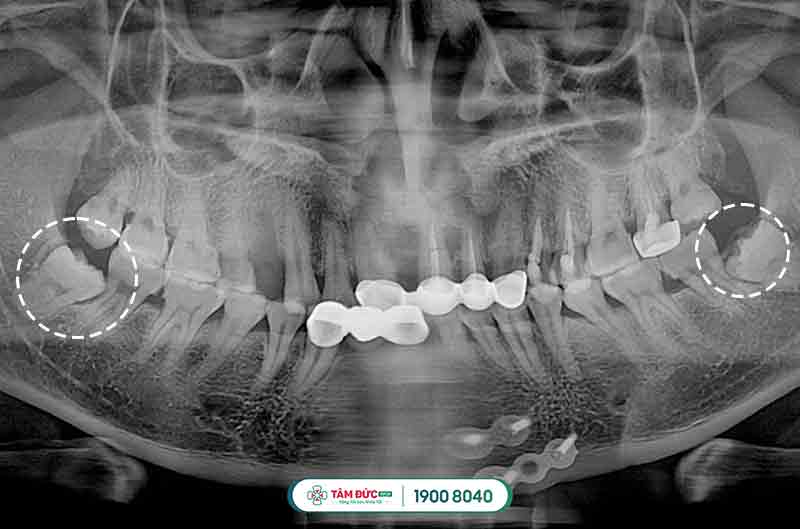

2.3.1. Tiến hành chụp phim X-quang

Chụp x-quang chiếc răng khôn mọc lệch để xác định vị trí, cũng như hướng mọc răng như thế nào rồi đưa ra phương pháp nhổ bỏ thích hợp nhất.